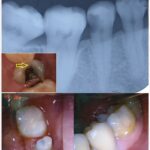

Beduya Dental Center is a TMJ-centered clinic which offer services specialized in TMD and Orofacial Pain, Orthodontics, Implantology, General Dentistry and Cosmetic Dentistry.